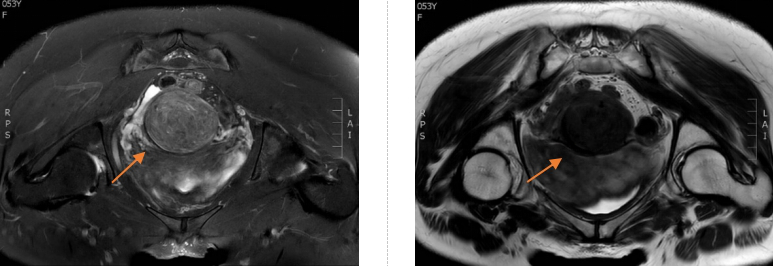

让冯女士惊喜的是,刘宾主任在充分评估她的病情与诉求后,当即联合妇科李冰琳主任团队展开多学科会诊,很快便给出了明确答复:“由于入院后盆腔MRI检查精准提示:子宫体下段可见一大小约:60mm×57mm×50mm 的占位性肿块,较前明显增大,已形成明确健康隐患。按照传统诊疗模式,子宫肌瘤切除术、双侧卵巢附件切除术与腹壁整形术、腰腹部精细化吸脂术需分两次实施,中间还要间隔数月恢复期。这不仅意味着要经历两次麻醉、两次创伤,腹部还会留下多处手术瘢痕,既增加了医疗风险,也延长了整体康复周期。而我们可以通过一体化联合手术方案,借助腹壁整形的精准切口同步开展妇科手术——无需额外增加创口,就能一次性完成病灶清除与形态修复。这样一来,既避免了二次手术的痛苦和麻醉风险,大幅缩短了恢复时间,还能最大程度减少瘢痕遗留,让治疗对身体的负担降到最低,同时满足健康保障与形态改善的双重需求。”